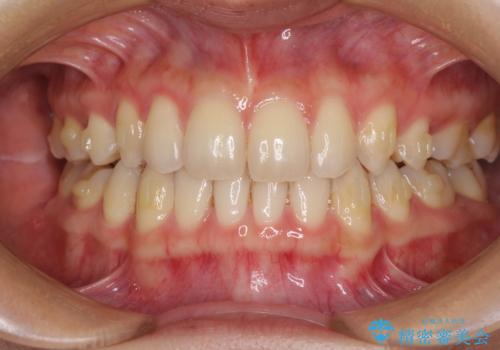

- 以前の矯正治療の後戻りにより、上の前歯にスペースができたことを気にして来院された患者様です。

インビザラインを用いて前歯のスペースを閉じつつ、上下の咬み合わせを構築していくこととしました。

隙間の空いてしまった前歯は、矯正治療で治療を行っても後戻りが起こりやすい傾向にあります。

マウスピースの保定装置をしっかりと装着しても空いてしまうため、細いワイヤーによる保定を併用することで後戻りを防止しています。